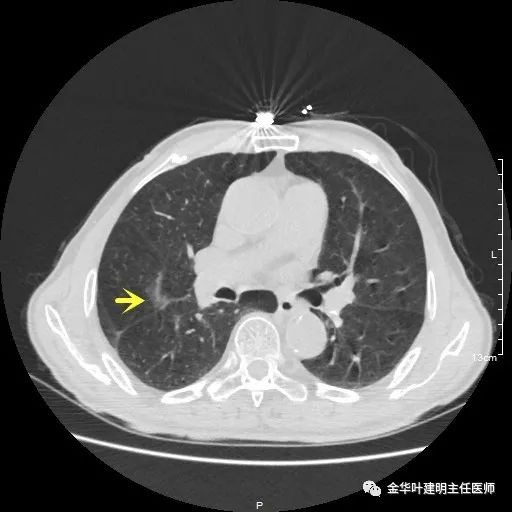

以上示右肺中叶病灶3。是混合磨玻璃结节,位置差,邻近肺门部,无法局部楔形切除,抗炎治疗后靶扫描显示了更清楚的细节,是典型的肺癌影像特征(此处未另提供)。从单病灶来看,需要行右肺中叶切除并清扫淋巴结才能得以治疗。